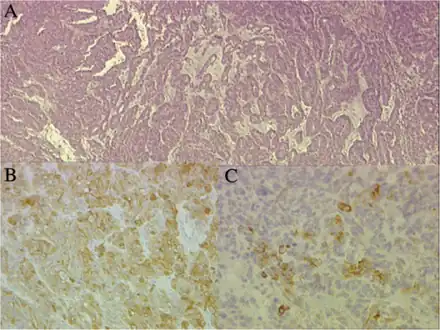

a)Papillary and tubular patterns represent the distinctive appearance of medulloepithelioma b)positivity of the neoplastic cells for S100 protein c) PanCytokeratin -

Neuronal differentiation, ranging from neuroblasts to ganglion cells, is seen in some medulloepitheliomas.

Histologically, medulloepithelioma resemble a primitive neural tube and with neuronal, glial and mesenchymal elements.[8][9] Flexner-Wintersteiner rosettes may also be observed.[10]

Immunohistochemically, neural tube-like structures are vimentin positive in the majority of medulloepitheliomas.[11] Poorly differentiated medulloepitheliomas are vimentin negative.